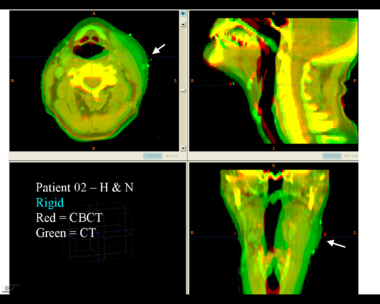

This first example shows the kind of anatomic changes that can occur in head and neck cancer. The pre-treatment scan is in green, and the mid-treatment scan is in red. The image on the left is the rigid registration, on the right is deformable registration.

Here is another pertinent example for head and neck. In axial view, there appears to be some weight loss. Note the change in positioning of the mandible, and also the twisting of the cervical spine between scans. Also note the strong CT artifacts caused by dental fillings. In both examples, registration of the soft palette is worse using deformable registration than rigid registration, probably due to these artifacts.